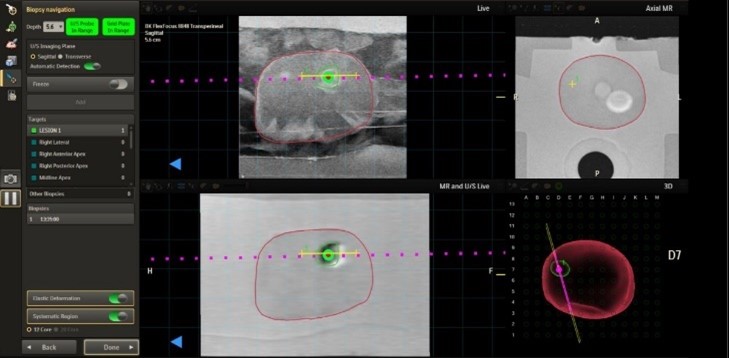

Amsterdam, the Netherlands – Royal Philips (NYSE: PHG, AEX: PHIA), a global leader in health technology, today announced a major advancement in image-guided navigation for prostate cancer care with the FDA 510(k) clearance of the latest Philips UroNav version. The system includes a new advanced annotation [1] workflow that supports clinicians during focal therapy procedures, helping deliver more precise, minimally invasive care.

As an image fusion system, UroNav seamlessly integrates pre-procedural imaging, such as Magnetic Resonance Imaging (MRI), with real-time intra-procedural imaging from ultrasound (US) systems. This innovative combination enhances the precision and accuracy of therapeutic procedures, providing clinicians with a comprehensive and dynamic view of the targeted area.

A more targeted approach means a more informed treatment selection and patients receive better and more precise care and clinicians are supported in better diagnosis, a 30% improvement in high-risk prostate cancer diagnosis using fusion biopsy compared to the standard biopsy [3]. The new advanced annotation workflow works in tandem with DynaCAD Urology to support focal therapy planning, deliver and review, reducing complexity and enabling a broader group of clinicians to offer minimally invasive options.

In addition to clinical functionality, Philips UroNav delivers enhanced compatibility with ultrasound devices and needle guides, upgraded privacy and security protections, and seamless integration with Philips DynaCAD systems for radiology and urology.

- DynaCAD urology with advanced annotation

- UroNav with advanced annotation